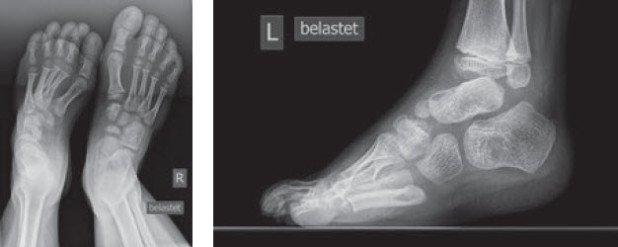

Bei diesem siebenjährigen Jungen zeigte sich eine äusserst steife Klumpfussdeformität links nach auswärtiger Behandlung. Der Patient wurde zuvor mit Gipsserien, einer «offenen» Achillessehnenverlängerung und später einer Nachtlagerungsschiene behandelt. Bei der Erstvorstellung in unserer Klinik belastete der Junge den Fuss ausschliesslich auf dem Aussenrand. Zusätzlich zeigte sich eine erhebliche Spitzfussstellung (Abb. 4 und 5). Das Röntgenbild offenbarte eine persistierende Klumpfussstellung mit typischer Parallelstellung des Sprung- und Fersenbeins (Abb. 6 und 7).